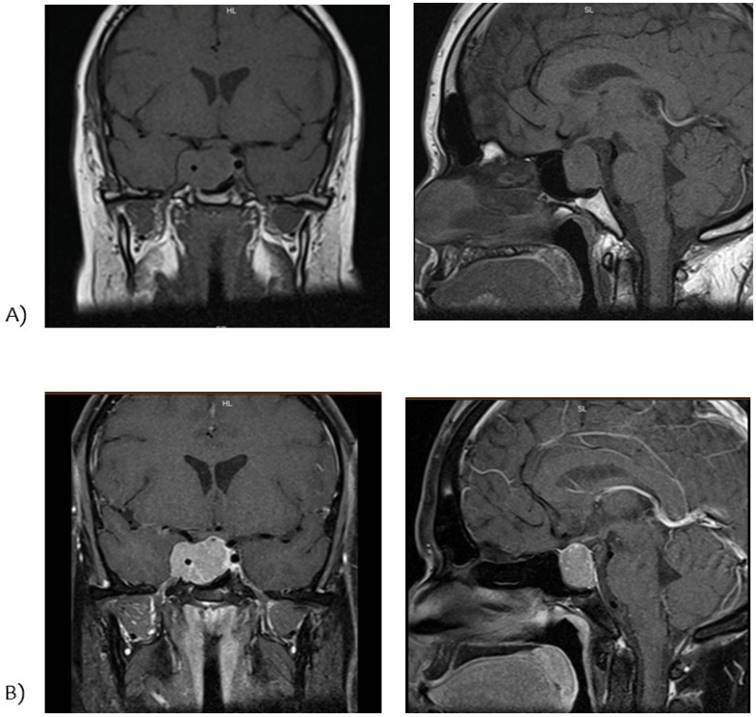

Se completa estudio de hipogonadismo hipogonadotrófico con la valoración del resto de los ejes hormonales (tabla 2) y resonancia nuclear magnética (RNM) de cráneo con enfoque selar (figura 1).

Figura 1: A) RNM de cráneo con enfoque selar conte coronal y sagital ponderada en T1. B) RNM de cráneo con enfoque selar conte coronal y sagital ponderada en T2.

RNM: lesión focal con epicentro selar de aproximadamente 37 x 28 x 19 mm en sus diámetros L, T y AP; invade el seno esfenoidal y el seno cavernoso derecho, englobando a la arteria carótida cavernosa en la totalidad de su circunferencia. Se extiende hacia la región supraselar, comprimiendo levemente el quiasma óptico; y un componente supraselar lateralizado a derecha que engloba la arteria carótida supraclinoidea. El tallo hipofisario se encuentra comprimido superiormente y lateralizado a izquierda. Resto del estudio normal (figura 1).

El diagnóstico del prolactinoma requiere evidencia imagenológica de adenoma. La resonancia magnética con gadolinio es el mejor procedimiento de imagen para la mayoría de las masas selares y, por lo general, no es necesario realizar ningún otro estudio de imagen (figura 1)9.